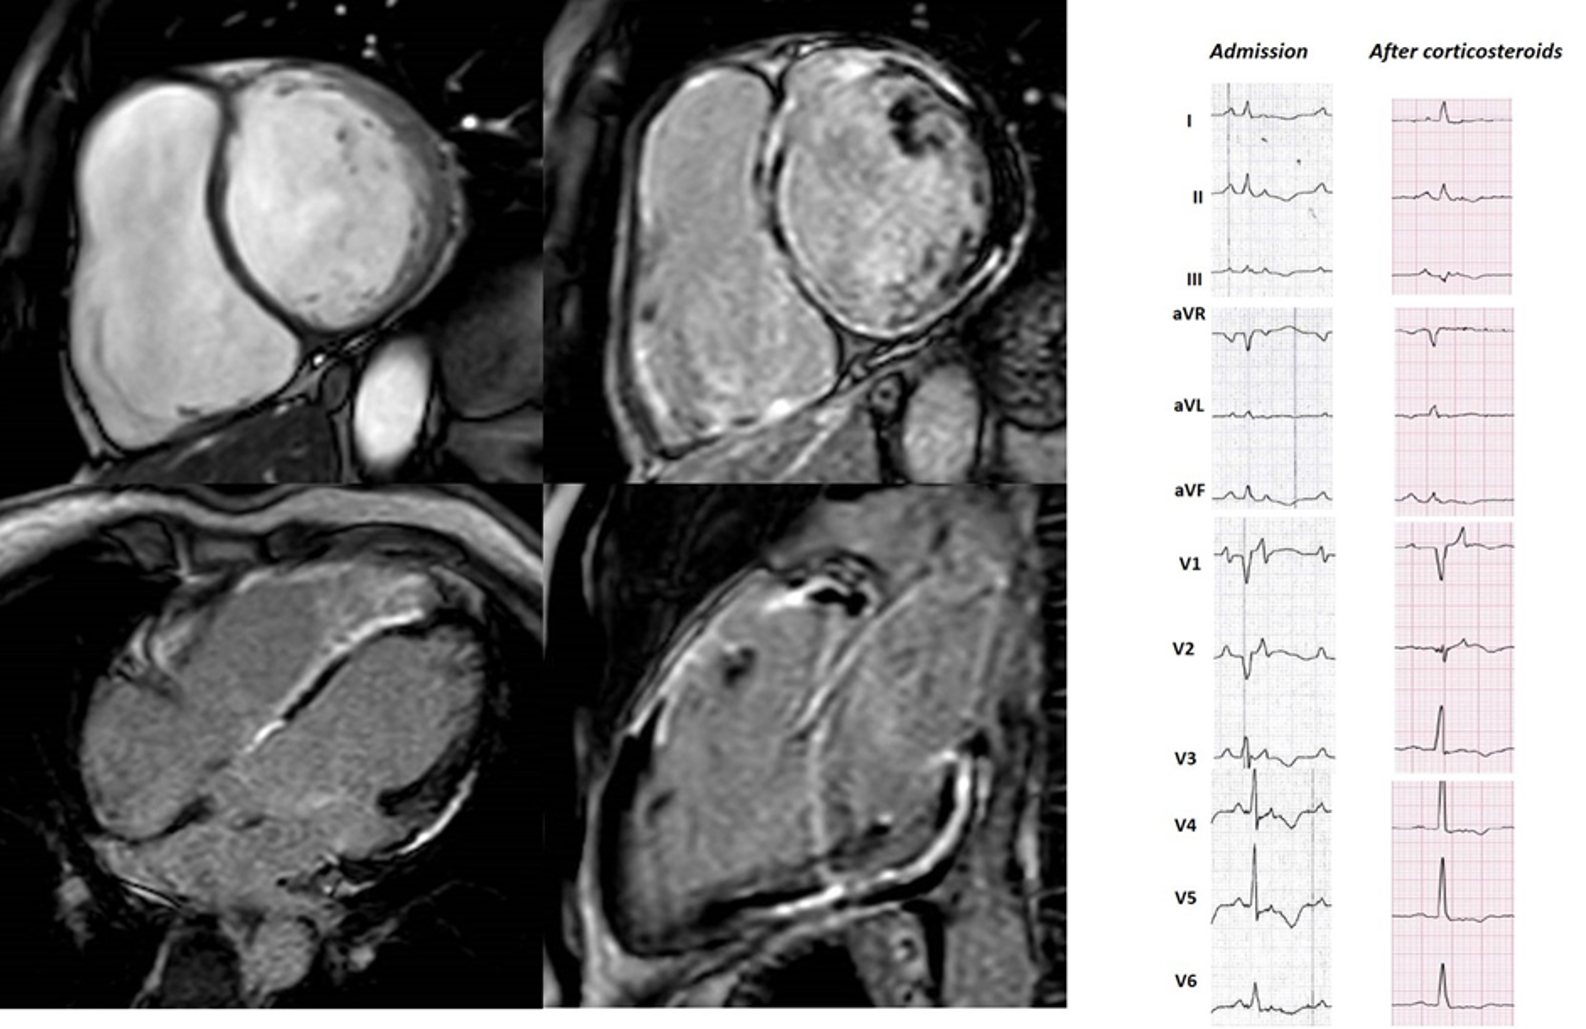

Fig. 4.48 years old male, endurance sportsman, with active sarcoidosis admitted in class 4 heart failure with recurrent slow monomorphic VTs. The ECG at admission mimics ARVC with a caricatural delayed high-amplitude epsilon wave and precordial T-wave inversion resulting in QT prolongation. Clinical improvement and partial ECG modification occurred after 30 days of steroid treatment. CMR showed biventricular enlargement and systolic dysfunction, with biventricular epicardial and midventricular LGE distribution. This case highlights the diagnostic challenges in ACM.